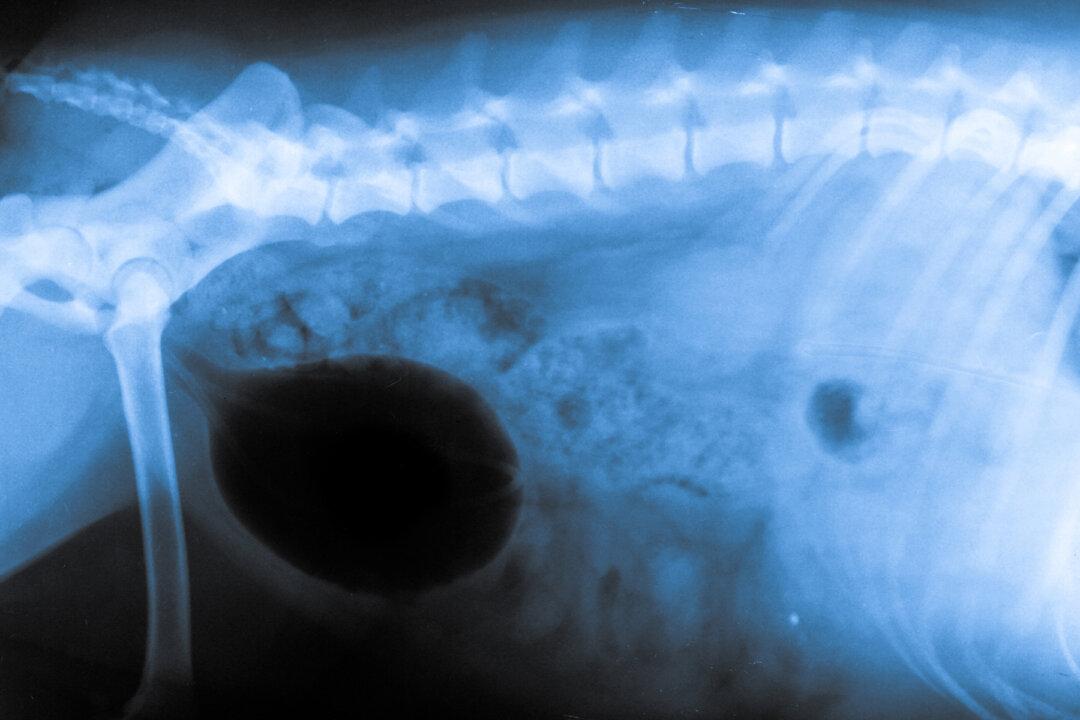

Cooper can’t help but keep smiling even though he has virtually no neck. In fact, the disabled American foxhound was born with a condition that’s even more limiting: he was born with literally only half a spine.

Cooper is just one out of 30 dogs in the world known to have the genetic condition called short spine syndrome, where the spinal vertebrae are compressed and fused together. It’s a condition said to be caused by inbreeding.